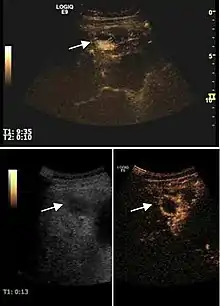

Liver cyst

Hydatid liver cyst. Diagnostic criteria are the presence of membranes and sediment inside.